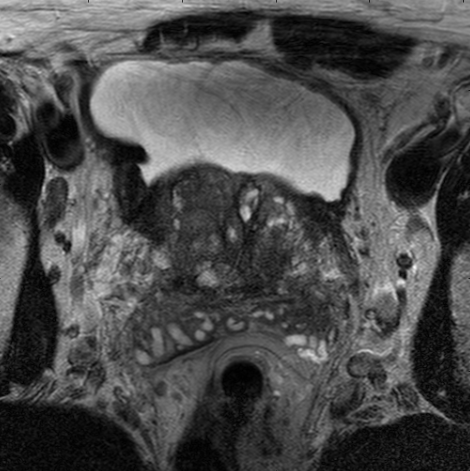

To intuitively compare the proposed method with U-Net and FCN, the segmentation results of some representative and challenging samples are shown in Fig 5. It can be seen that these prostate images have fuzzy boundaries and the pixel intensity distributions are inhomogeneous both inside and outside of the prostate. Besides, both prostate and nonprostate regions have similar contrast and intensity distributions. All of these phenomenons make the segmentation difficult.

As shown in the second column in Fig 5. FCN model failed to obtain satisfactory result, though the model could detect part of prostate. However, for the details of prostate, for instance, the boundaries, the network can not assign the label to each pixel accurately.

In U-Net model, the label has be assigned to each pixel and has improved the segment accurate as shown in the third column in Fig 5. However, the network always make a mistake when assigning the label to nonprostate regions. Besides, for the boundaries information, the network cannot work well. At last, the segmentation results lose some important information and there still exist some errors.

The results of deeply supervised CNN are shown in the fourth column of Fig 5. The fuzzy boundaries are well detected by our proposed method. Besides, the segmentation boundary are more continuous and smooth than the competing method. It can be proved that additional supervised layers are useful for the texture and boundaries of prostate.